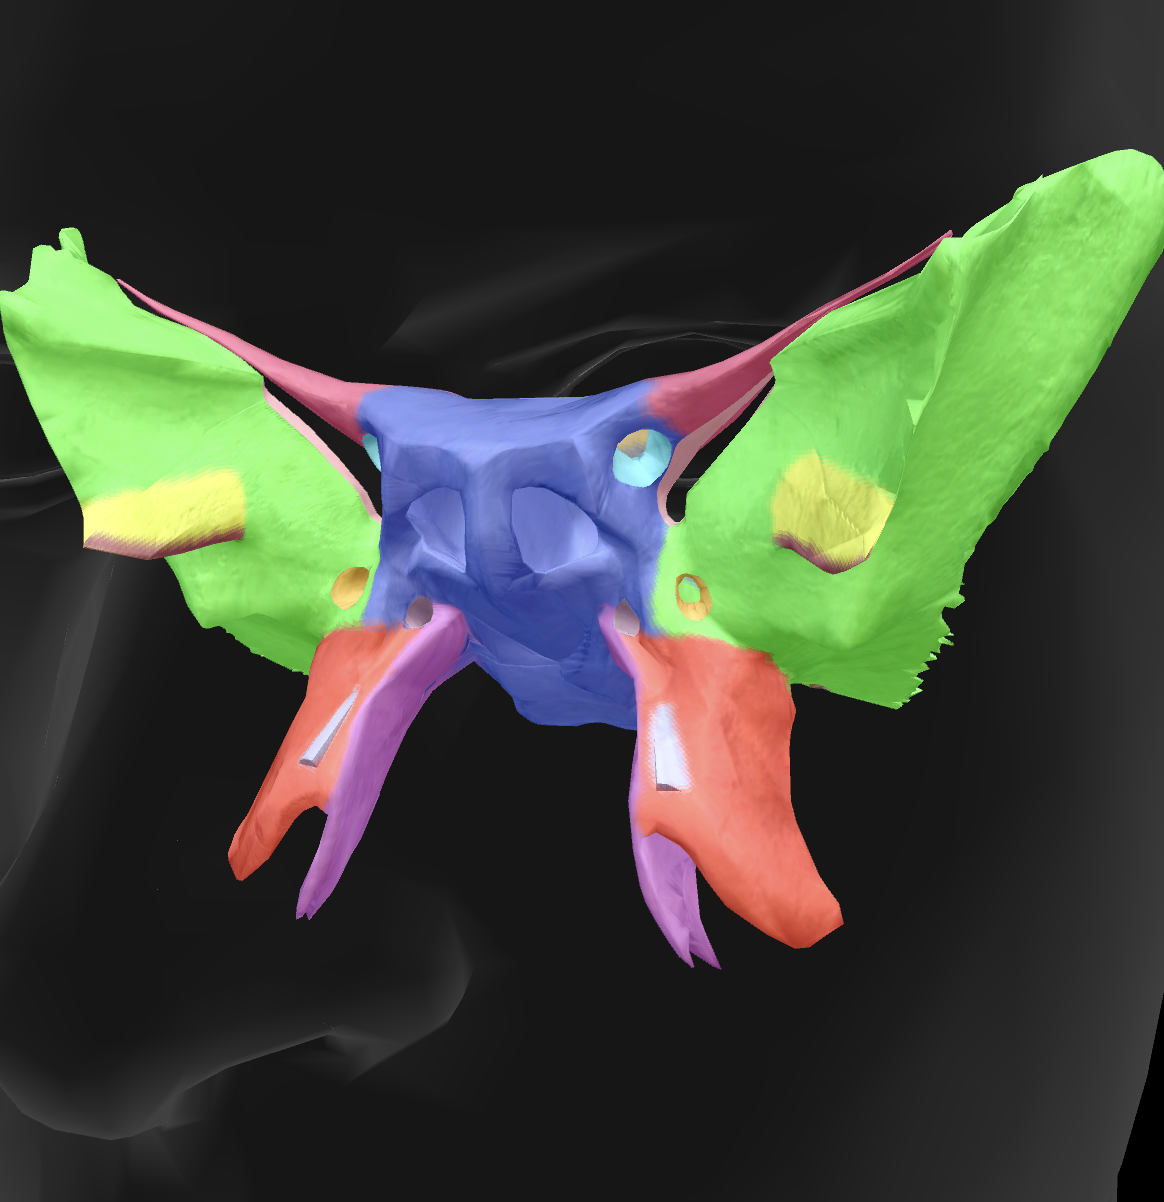

What is the name of this bone?

sphenoid bone

body

What is the name of this feature?

lesser wings

What is the name of this feature?

sella turcica

What is the name of this feature?

greater wings

What is the name of this feature? (the hole)

optic foramen

What is the name of this feature?

lateral pterygoid plate

What is the name of this feature?

medial pterygoid plate

What is the name of this feature?

superior orbital fissure

What is the name of these holes?

foramen rotundum

What is the name of these holes?

foramen ovale

What is the name of these holes?

foramen spinosum